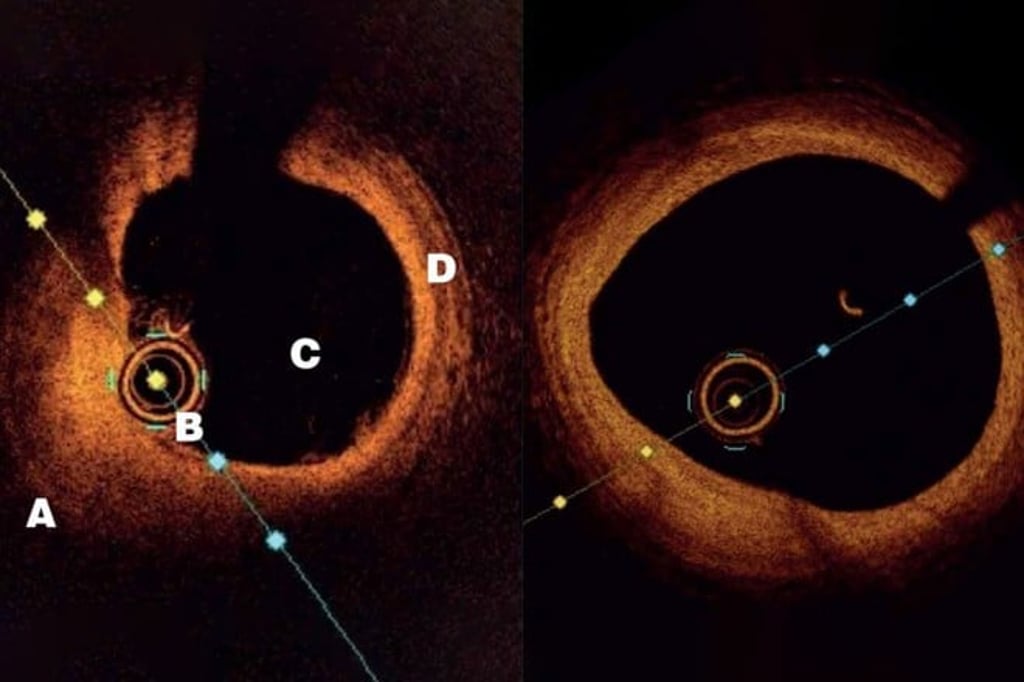

“We can now look at an artery from the inside with HD imagery that shows great details of the plaques. We can see whether they’re old or new, have calcium or are easy to rupture, which greatly improves our diagnostics,” said Dr. Cheong. This advanced imaging technique, called Optical Coherence Tomography (OCT), involves inserting a tiny and flexible catheter into the artery. Using lightwaves near infrared range, OCT allows the doctor to analyse the histology of the plaques(5).

“I have a patient who had a major heart attack in his 30s in London in the 2000s. He came to Hong Kong to work and I had to touch up on his stent procedure. Part of his vessels had plaque buildup so I prescribed both a statin and a PCSK9 inhibitor. Three years later, I looked at his artery again and the improvement was remarkable. There was less deposit on the artery wall and his cholesterol was reduced to a very low level,” said Dr. Cheong.